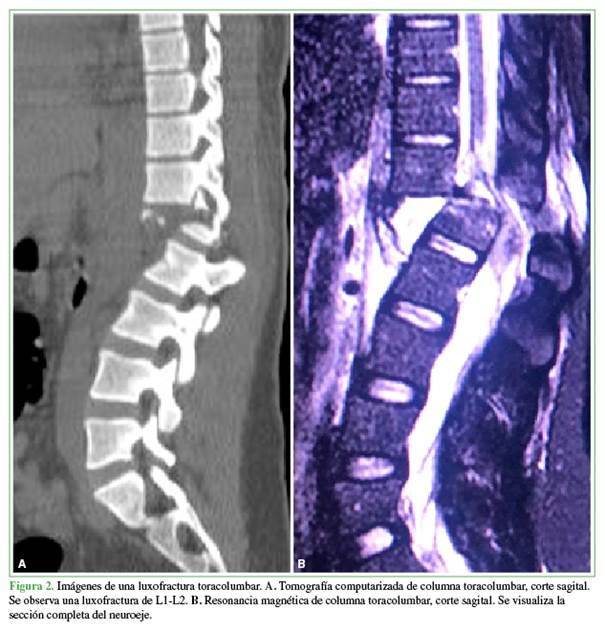

Se registraron 283 complicaciones en 67 (93,1%) pacientes. Se produjeron 45 complicaciones quirúrgicas en 26 pacientes (36,1%), 22 de ellas (48%) eran grado III de la clasificación de Clavien-Dindo (“complicaciones que requieren alguna intervención quirúrgica, endoscópica o radiográfica”) (Tabla 2, Figura 2).